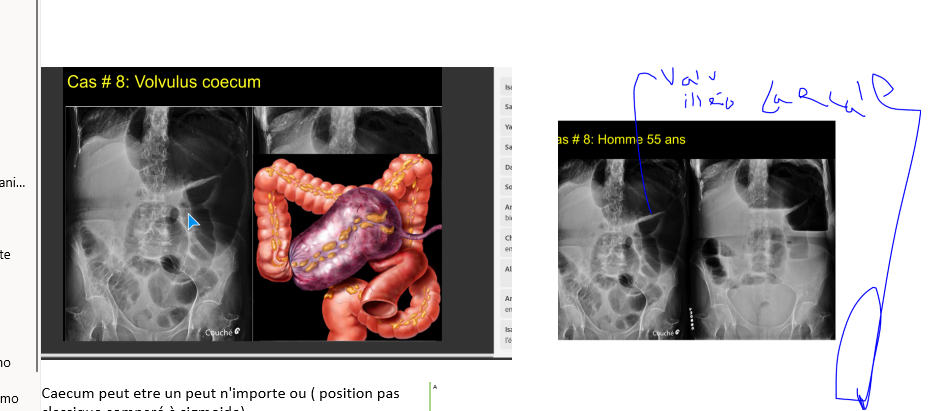

Q

diagnostic?

A

volvulus pck immense

mais pas de grain de café so

volvulus du CAECUM